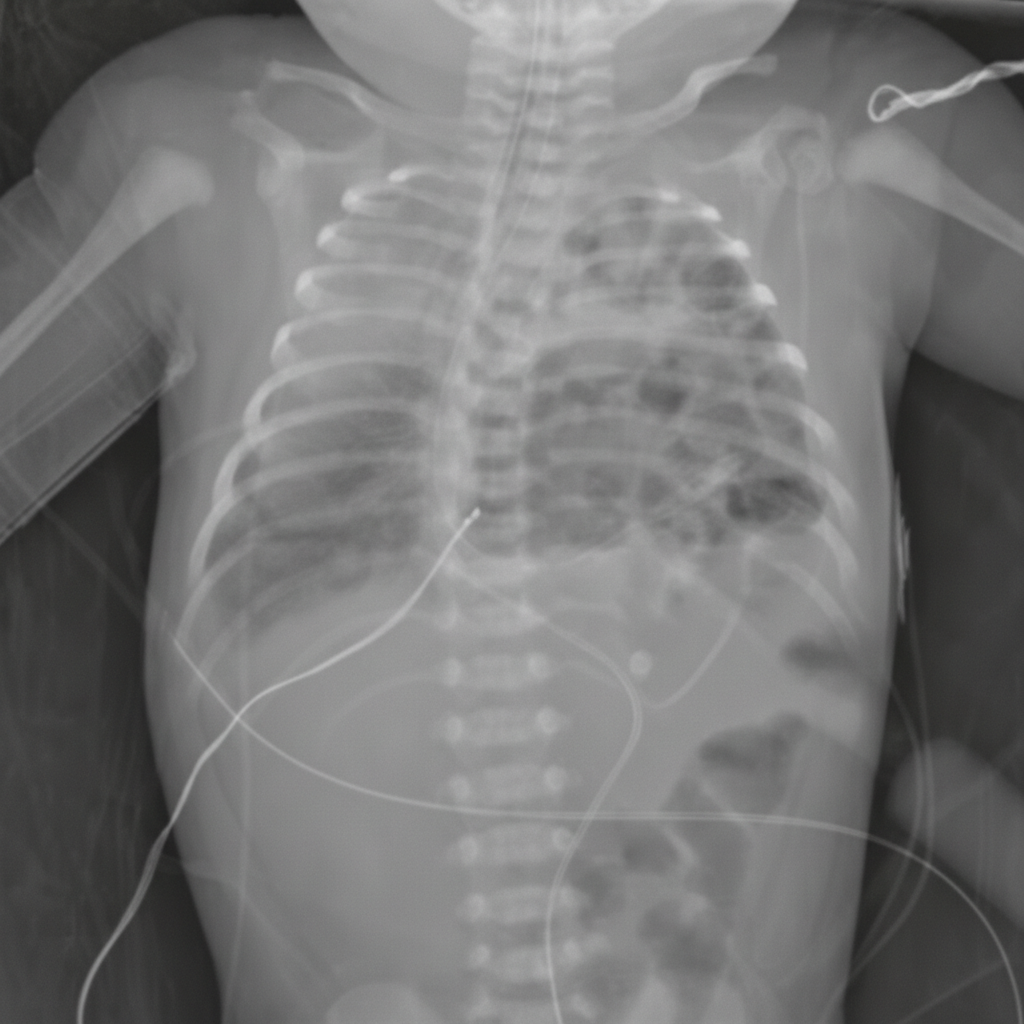

A 3900-g (8.6-lb) newborn is delivered at 38 weeks' gestation to a 27-year-old woman, gravida 3, para 2, via spontaneous vaginal delivery. Immediately after delivery, he spontaneously cries, grimaces, and moves all four extremities. Over the next five minutes, he becomes cyanotic, dyspneic, and tachypneic. Mask ventilation with 100% oxygen is begun, but ten minutes after delivery the baby continues to appear cyanotic. His temperature is 37.2°C (99.0°F), pulse is 155/min, respirations are 65/min, and blood pressure is 90/60 mm Hg. Pulse oximetry on 100% oxygen mask ventilation shows an oxygen saturation of 83%. Breath sounds are normal on the right and absent on the left. Heart sounds are best heard in the right midclavicular line. The abdomen appears concave. An x-ray of the chest is shown below. Which of the following is the most appropriate initial step in the management of this patient?